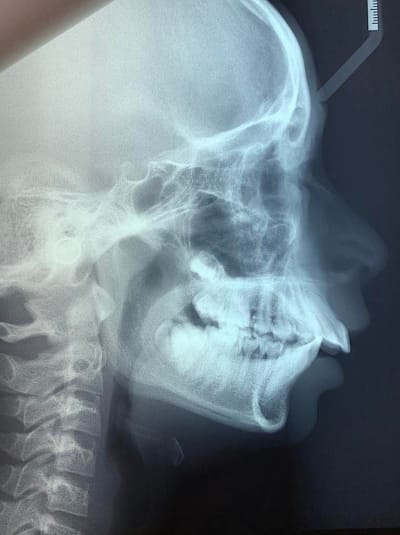

Je souhaiterais avoir vos avis sur le traitement orthodontique de ce cas : Classe II division 1 importante avec biproalvéolie.

Je vous communique mes données céphalo :

SNM 29

FMA 20

SNA 89

SNB 77,5

ANB 11,5

I/F : 57

IMPA 115

FMIA 44,5

AoBo 8

Peut-être que les confrères d'eugenol me contre-diront, mais je ne vois pas du tout de promaxillie sur cette radio de profil. Une proalvéolie maxillaire ok, mais pas de promaxillie. Pour être honnête, j'ai tendance à penser que les classes II sont issues de rétromandibule de façon très très générale, et à peu près jamais de promaxillie. Autant je suis bien d'accord qu'une mandibule peut se développer à l'excès et donner une promandibulie, autant je n'ai encore jamais vu de maxillaire qui se développerait au delà de la norme.